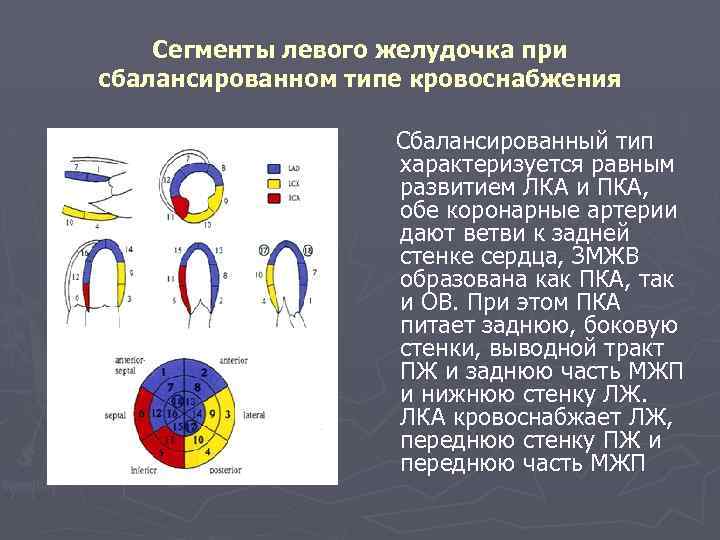

Сегменты левого желудочка при сбалансированном типе кровоснабжения Сбалансированный тип характеризуется равным развитием ЛКА и ПКА, обе коронарные артерии дают ветви к задней стенке сердца, ЗМЖВ образована как ПКА, так и ОВ. При этом ПКА питает заднюю, боковую стенки, выводной тракт ПЖ и заднюю часть МЖП и нижнюю стенку ЛЖ. ЛКА кровоснабжает ЛЖ, переднюю стенку ПЖ и переднюю часть МЖП

► Европейская ассоциация эхокардиографии рекомендует использовать наиболее часто встречающийся тип кровоснабжения для оценки нарушения кровоснабжения. «Левый тип» кровоснабжения: ► 6, 5, 11 и 12 -й сегменты питает правая коронарная артерия; ► 4, 10, 3 и 9 -й- левая огибающая; ► 1, 2, 7, 8, 13 и 15 -й- левая передняя нисходящая коронарная артерия ►